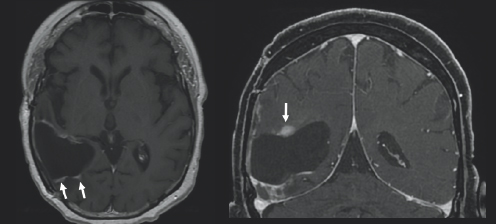

(Left) There is charcoal grey color surrounded by black space and a thin light grey outline. On the left side of the image, there is a black blob with two small white blobs beneath it which are highlighted by two small white arrows. (Right) There is charcoal grey color surrounded by black space and a thin light grey outline. On the left side of the image, there is a black blob with a white spherical figure above it with is highlighted by a small white arrow.

FIGURE 3.2 Brain MRI after surgery. Axial (right) and coronal (left) post-contrast images show postoperative changes from resection of the mass. Follow-up post-contrast images, obtained 29 months follow-up, demonstrate new nodular areas of abnormal enhancement that appear bright after being injected with IV contrast, along the superior and anterolateral margins of the resection cavity (white arrows), concerning for recurrent tumor.

A month after her surgery, Janet began chemotherapy and radiation treatment. She began trialing different chemotherapy drugs recommended by her team of physicians to pinpoint which would be most effective for her tumor. She was unable to be treated with the standard-of-care drug, TMZ, due to a severe anaphylactic allergic reaction. Despite desensitization to try to ween her on TMZ use, she continued treatment with lomustine, a different chemotherapy drug. Janet was placed on multiple clinical trials starting with the Belinostat/MRSI (magnetic resonance spectroscopic imaging) study and later the 5-ALA (5-aminolevulinic acid) study. Early on in her treatment, Janet turned to tumor treating fields (TTFs), to see if that form of treatment could provide her the benefit of tumor reduction. TTFs are commonly used in the form of an Optune® device. An Optune® device is a physical, white-colored cap that patients can place over their shaved heads to reduce cancer cell growth through the electric fields that the device omits. In the fall of 2019, Janet moved her care from Emory University Hospital and Wake Forest Hospital to the University of Cincinnati Medical Center to follow her neuro-oncologist, Dr. Soma Sengupta, with whom she had formed a close relationship. Due to the progression of her disease Janet underwent a re-resection surgery in March of 2020 and was placed on the adjuvant letrozole drug study. She then started the chemotherapy drug bevacizumab and required stereotactic radiosurgery (SRS) for a new lesion (Fig. 3.2–3.4). She continued care through her doctors in Cincinnati in conjunction with the care she was receiving at Wake Forest Hospital. She felt prepared but nervous each time she underwent imaging because she knew if her tumor had grown, it would result in a change of course to her treatment.